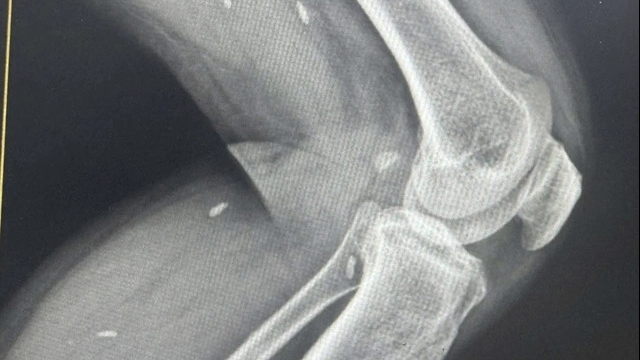

Theo người nhà, bệnh nhân có tiền sử đau khớp, viêm mũi và đã mua thuốc trên mạng để điều trị. Thuốc này được mọi người truyền tai nhau là tốt nên một số người dân trong làng đã nhập về bán số lượng lớn với giá 10.000 đồng/gói.

| Thuốc bệnh nhân K.T.S mua để uống |